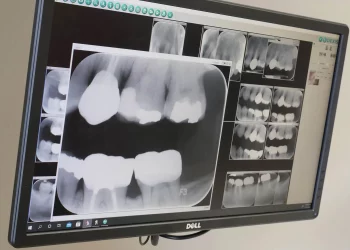

How Have Digital X-Rays Evolved, and Why Are They Considered Safer Today?

Introduction The field of dentistry has experienced remarkable advancements in diagnostic technologies, with digital X-rays emerging as one of the ...